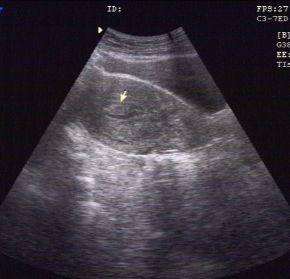

一位41岁,有月经经期延长半年,妇科超声描述:宫腔内见高回声区13mm×6mm,提示:子宫内膜息肉。

子宫内膜息肉的无创检查,首选妇科超声检查,推荐经阴道超声(有*生活性**史的女性)或经直肠超声(无*生活性**史的女性)。一般妇科超声检查的时间选择月经周期的第5-7天(早卵泡期)为最佳。但即使超声有上述提示子宫内膜息肉,并不等于确诊。